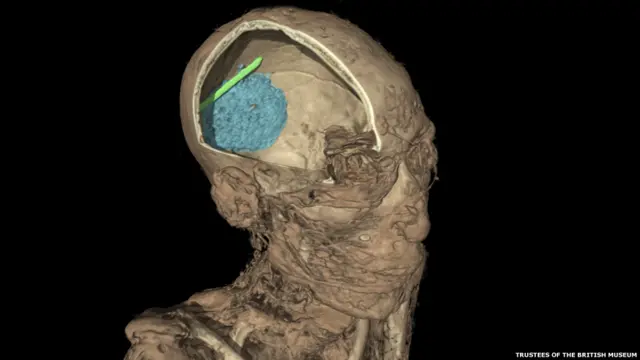

Новая экспозиция в Британском музее с помощью самых передовых технологий дает зрителю шанс заглянуть в прошлое и прикоснуться к жизни древних египтян.